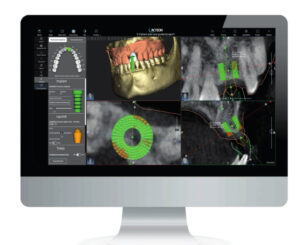

Tomograf X-mind Trium

Tomograf komputerowy będący nowatorskim system do obrazowania cyfrowego. X-Mind Trium wyposażony jest w algorytm akwizycji i rekonstrukcji, zapewniający najwyższej jakości obrazy dla wszystkich projekcji.

Sprzęt ten gwarantuje duże bezpieczeństwo pacjentów, dzięki znacznie ograniczonemu narażeniu badanego na promieniowanie. Innowacyjny algorytm redukuje natężenie prądu (mA) o 50% zmniejszając dawkę pochłoniętą przez pacjenta, nie powodując przy tym utraty jakości obrazu!

Tomograf X-MIND® trium 3D znacznie przyspieszających pracę implantologa. Przestrzenna mapa gęstości kości wokół planowanego implantu pozwala na uzyskanie pełnej informacji i zwiększenie bezpieczeństwa zabiegu.

W TROSCE O NAJMŁODSZYCH

Aby chronić dzieci wprowadzony został dodatkowy ruch czujnika, który pozwala zbliżyć go do głowy i jeszcze bardziej obniżyć dawkę pochłoniętą przez małego pacjenta.